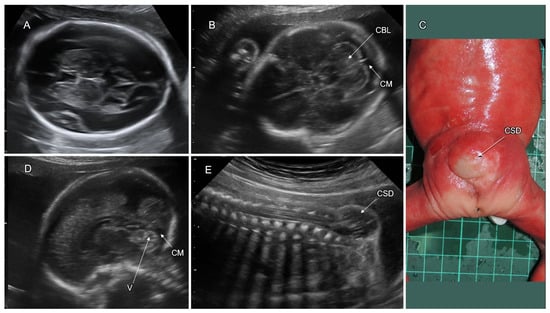

6.2.2. Cobblestone Malformation (CM)

7.8. PF Anomalies Associated with Cobblestone Malformation (CM)